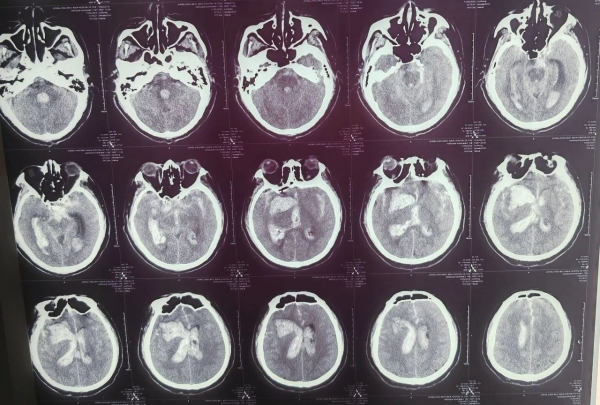

CT檢查發(fā)現(xiàn)張大叔

右側(cè)基底節(jié)區(qū)大量腦出血破入腦室

并伴有腦疝

確診為腦出血

(術(shù)前)